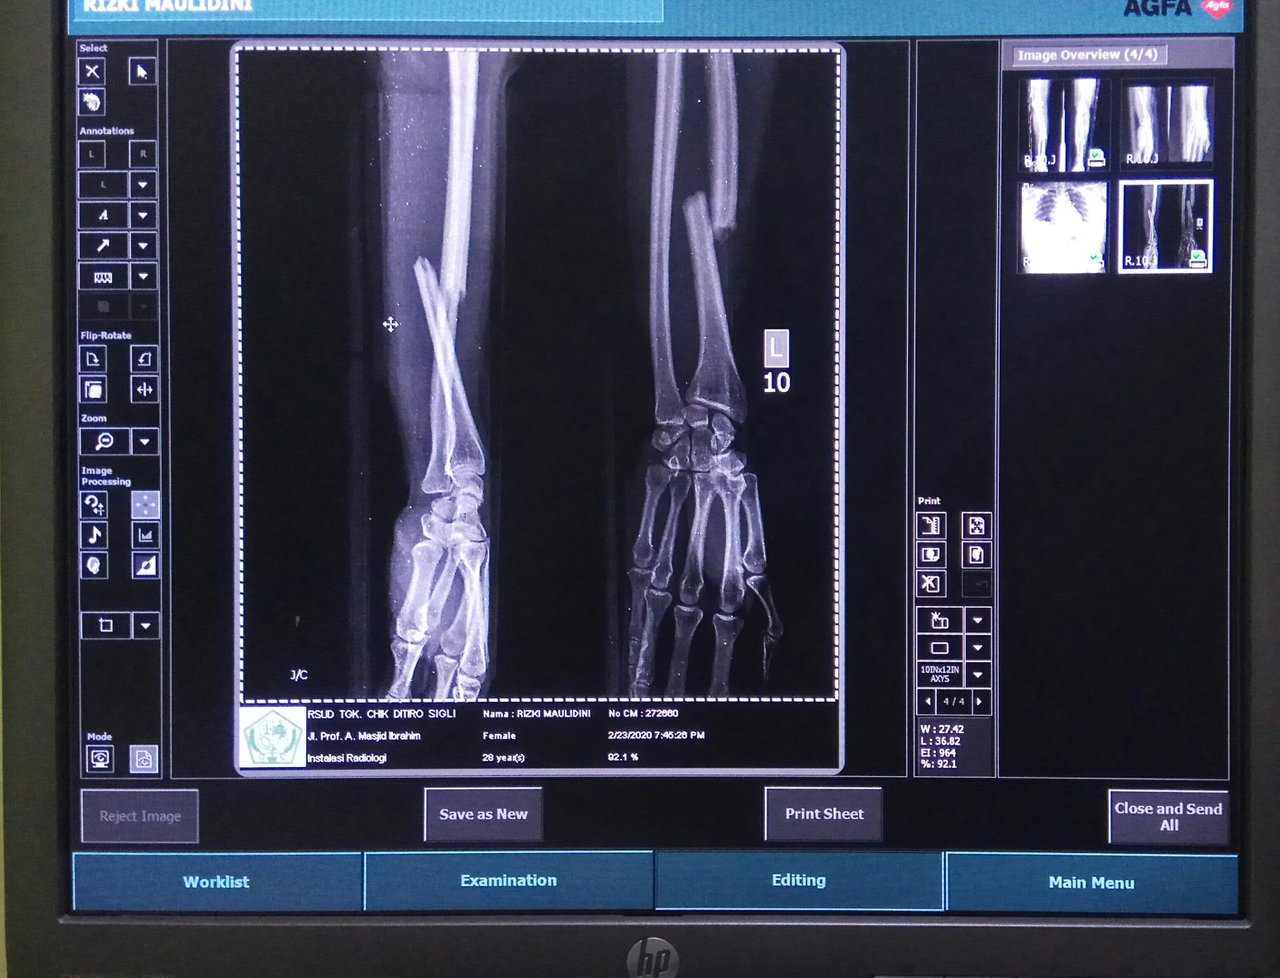

The woman was diagnosed with fractures in the right arm and left arm. Also experiencing dislocation on both wrists. It also experienced pain in the chest. So the doctor in charge of the emergency department requested a radiological examination of these organs.

The first is that I examine my left arm and left wrist. Then I did a check on his right arm and right wrist. After that I asked the patient's family to take off the patient's clothes and use the replacement clothes that we had provided. Because I have to do an inspection on the chest. In addition to clothes, also must be removed BH. Also the necklace must be removed. This is so that later in the image produced after radiological examination, there is no shadow of these objects.

After completing radiological examination, the resulting image showed that this woman had fractures in both arms and also had dislocations on both wrists. While in the chest and ribs there is no visible abnormality.